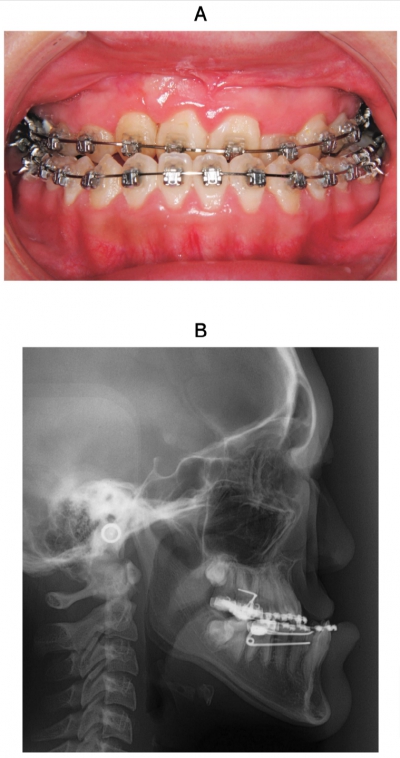

19歳の女性。反対咬合を主訴として来院した。術前矯正治療後に顎矯正手術を行うこととした。術前矯正中の口腔内写真、頭部エックス線規格写真及び手術中の写真を示す。

行っている手術はどれか。1つ選べ。

c. Le FortⅠ型骨切り術

d. Obwegeser-Dal Pont法